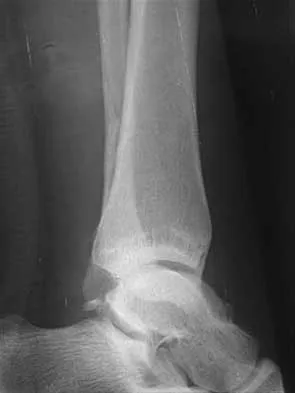

A 12-year-old boy with an ankle fracture undergoes closed reduction under sedation in the emergency department. Figure 27 shows a lateral radiograph of the ankle after two attempts at closed reduction. Based on these findings, treatment should now consist of

Detailed Explanation